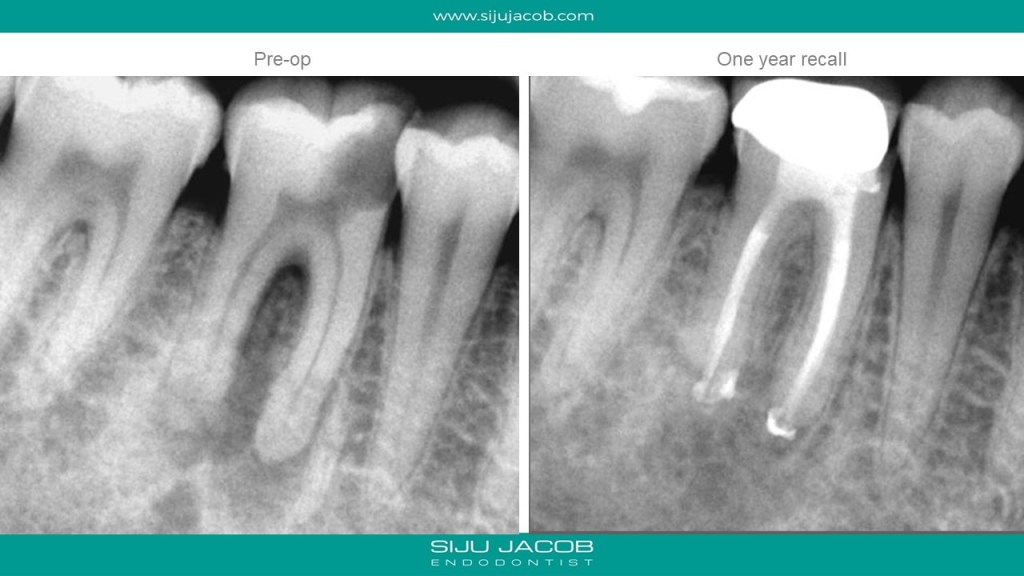

This is a garden variety middle-mesial canal i tretaed in 2009. The crown done by the referral was a bummer. Patient came back a year later with discomfort. The periapical lesion had healed, but the crown had an open margin leading to food impaction. I suggested changing the crown. Liviu Steier requested that I convert this case into a small article for Dental tribune U.K. Attached is the pdf from 2009.